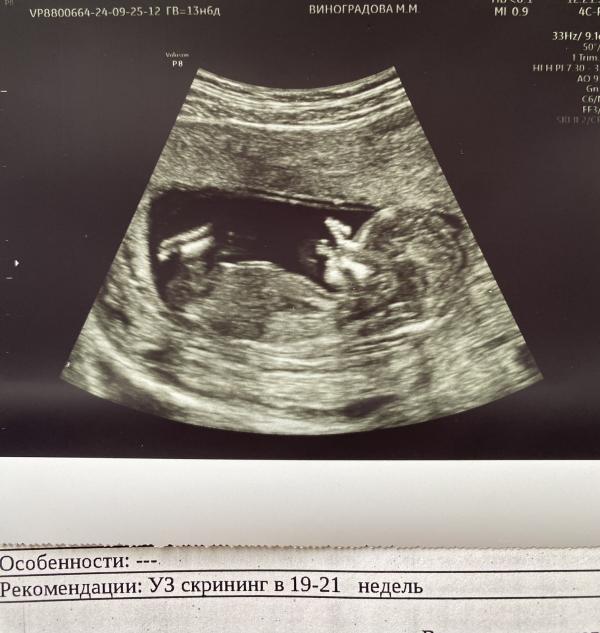

Девочки, тут видно бугорок? Смотрела в записях у других, сравнивала, ничего не увидела. У врача спросила, когда уже закончилось узи, она сказала что предположительно мальчик, нашла фото яичек, там вроде и правда они, но кроме их больше нет ничего, ничего не торчало. И в интернете пишут, что до 15 неделе нет самих яичек. На второй скрининг 15 ноября. Рс, у меня 3 сына и до 2 скрининга не говорили пол. С третьим сдавала кровь на определение пола. Со вторым как-то сразу поняла что там сын. Сейчас беременность очень отличается от предыдущих. С предыдущими с первых недель ела все соленое, огурцы, рыбу и т.д. А с этой, не зная еще что беременна, ела шоколад, тортики, пирожные и до сих пор так. За раз 1-2 плитки шоколада съедаю и мне все мало. Заранее спасибо за ответы 🙏🏻🌹 #первыйпост

У меня на момент скрининга было 13.6 ) после не ходила еще. 15 ноября на второй скрининг

Яички ещё не видно на этом сроке.

Вот и я о том же подумала, когда уже вышла из кабинета. Потом начала гуглить. Как могли увидеть яички на таком сроке, не знаю. Но и комментарии тут читала, у кого-то яички видели и в 12 недель 🙈